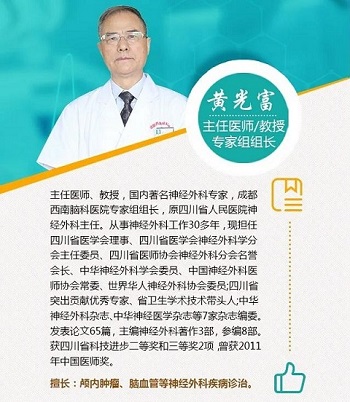

经我院黄光富教授团队手术治疗,术后张女士自觉心情平静很多,不再乱发脾气,也没有再出现梦游的现象,睡眠也好了很多,张女士及其家人对治治疗果很满意!